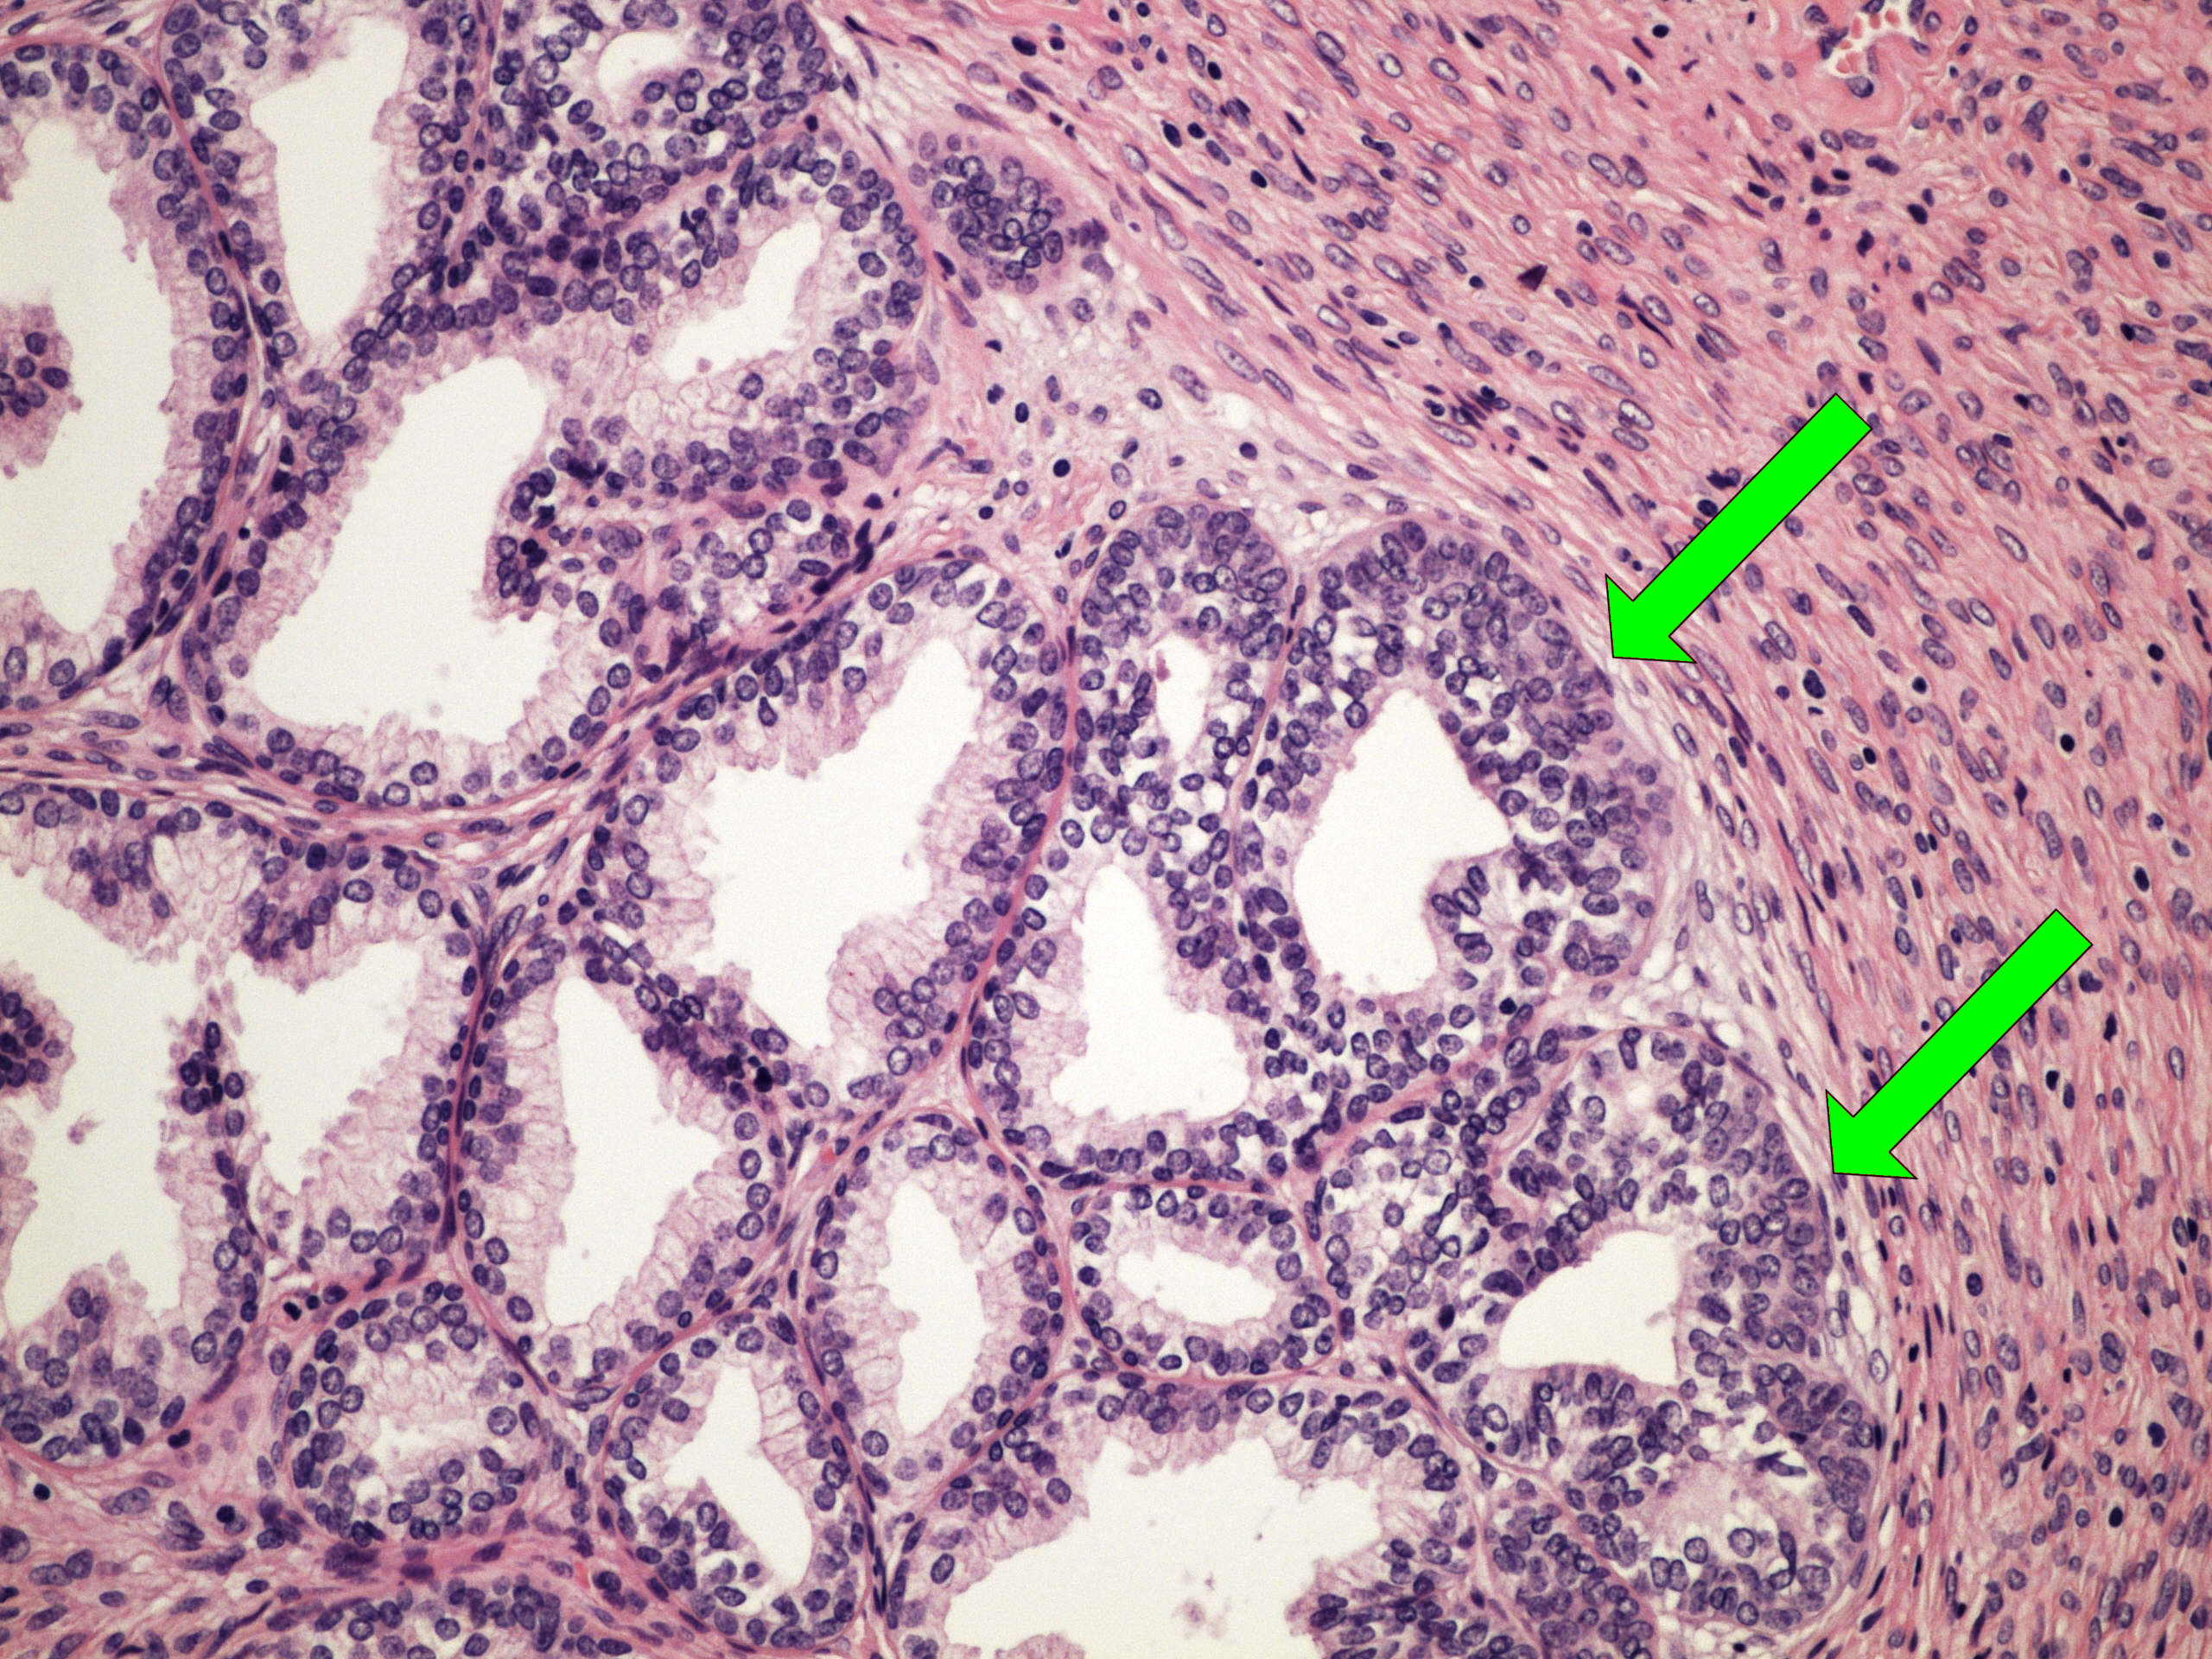

Preparát č.15 a č.16 - hyperplasie prostaty

Struktury

- stroma

- žlázky

- vrstva bazálních buněk (charakt. pro hyperplazii)